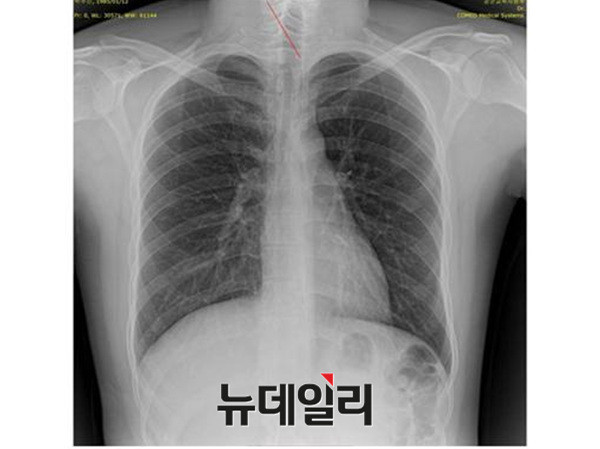

박원순 서울시장의 아들 박주신씨 병역비리 의혹과 관련돼, 세계적으로 권위를 인정받고 있는 해외 의학자들이, 박주신씨 명의의 엑스레이 사진에 대한 판독결과, 피사체를 동일인으로 볼 수 없다는 의학적 소견을 내놨다.

박주신씨의 신체를 촬영한 엑스레이는 모두 3개가 존재한다. 첫 번째는 2011년 12월 촬영된 자생병원 엑스레이이며, 두 번째는 박주신씨가 2011년 8월 공군에 입소하면서 본인 확인 후 촬영한 엑스레이다. 세 번째 엑스레이는 지난해 7월 주신씨가 영국 출국에 앞서 비자 발급을 위해 연세대 세브란스병원에서 새로 촬영한 것이다. 이들 3개의 엑스레이 가운데 자생병원 엑스레이에 대해서는, 주신씨 본인이 아닌 대리신검자가 촬영한 것이라는 의혹을 받고 있다.

의료혁신투쟁위원회(공동대표 정성균, 최대집, 이하 의혁투)는 27일 “박주신씨 병역비리 의혹에 대한 단순 방사선 사진(X-RAY)을 국제학회에 보내 객관적인 의학적 소견을 받았다”며, 아시아근골격의학회 사무총장이 보내온 소견서를 공개했다.

의혁투가 공개한 소견서는 아시아근골격학회 사무총장을 맡고 있는 스리 안드리아니 우토모 교수가 작성한 것으로, 박주신씨가 지난해 7월, 영국 출국 비자를 발급받기 위해 연세대 세브란스병원에서 촬영한 엑스레이(A)와, 2011년 12월 촬영된 자생병원 엑스레이(B)를 동일인의 것으로 볼 수 없다는 의학적 소견을 담고 있다.

의혁투는 아시아근골격학회에 보낸 의견 조회서에서, 박주신씨 명의의 두 엑스레이에서 나타나는 대표적 차이점인 ▲경추7번 및 흉추1번 척추골(극상돌기) ▲우측 늑골 1번의 ‘석회화 현상’ ▲전체적인 흉곽의 형태 ▲쇄골 형태의 차이 ▲하행 대동맥의 음영 등에 대해 질의했다.

이에 대해 우토모 교수는 위의 모든 항목에서, “두 엑스레이는 서로 다르다”는 견해를 분명히 밝혔다.

앞서 의혁투는 지난 10일 서울프레스센터에서 기자회견을 열고, 박주신씨 병역비리 의혹과 관련된 의학적 쟁점에 대해, “영상의학과, 정형외과, 재활의학과, 신경외과, 내과 전문의 등의 소견을 청취한 결과, 박주신씨 명의의 엑스레이 영상자료에서 병역비리 의혹을 뒷받침하는 차이점을 발견했다”고 밝힌 바 있다.

이에 대한 근거로 최 대표는 “2011년 12월 자생병원에서 찍은 엑스레이에서는 우측 제1늑골에 석회화 소견이 발견되고, 흉추 1번 극상돌기 역시 수직방향으로 배열돼 있지만, 공군 엑스레이와 비자발급용 세브란스병원 엑스레이에서는 석회화 현상이 발견되지 않았고, 극상돌기 역시 오른쪽 방향으로 배열돼 있다”고 설명했다.